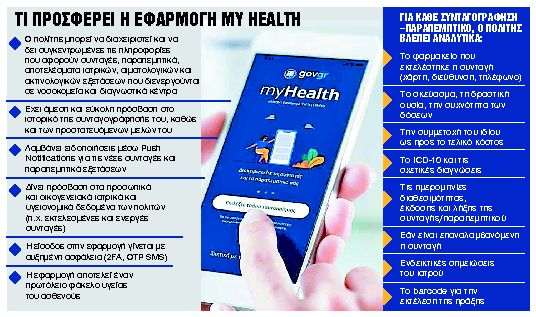

Στο κινητό ο πλήρης ιατρικός φάκελος

Οι χρήστες αποκτούν πρόσβαση στα ιατρικά και υγειονομικά τους δεδομένα και θα μπορούν να βλέπουν όλες τις συνταγές και τα παραπεμπτικά - Τα δύο νέα e-πιστοποιητικά

Τον πλήρη ιατρικό φάκελο με τις συνταγές, τα παραπεμπτικά, καθώς και τα αποτελέσματα όλων των ιατρικών, αιματολογικών και ακτινολογικών εξετάσεων που διενεργούνται στα νοσοκομεία και τα διαγνωστικά κέντρα θα έχουν πλέον στο κινητό τους τηλέφωνο όλοι οι πολίτες που χρησιμοποιούν την ψηφιακή εφαρμογή my Health.

Τα υπουργεία Ψηφιακής Διακυβέρνησης και Υγείας προχώρησαν χθες στον εμπλουτισμό της εφαρμογής my Health app, η οποία μέχρι τώρα συγκέντρωνε πληροφορίες μόνο για τη συνταγογράφηση και τα ιατρικά παραπεμπτικά.

Μέσω της πλατφόρμας my Health, που είναι ενταγμένη στο gov.gr, οι πολίτες έχουν πλέον πρόσβαση σε νέες ψηφιακές υπηρεσίες υγείας, αποκτώντας για πρώτη φορά ψηφιακό φάκελο και ιστορικό ασθενούς και μειώνοντας δραστικά τη γραφειοκρατία, τις περιττές επισκέψεις και τα ογκώδη έγχαρτα νοσοκομειακά αρχεία.

Ψηφιακά αντίγραφα

Ειδικότερα, οι πολίτες μπορούν πλέον να αποθηκεύουν ψηφιακά (στο κινητό, το τάμπλετ ή τον Η/Υ) όλες τις ιατρικές εξετάσεις και τις βεβαιώσεις νοσηλείας που έχουν εκδοθεί για τον ΑΜΚΑ τους από γιατρούς και νοσοκομεία-διαγνωστικά κέντρα. Τα ψηφιακά αντίγραφα περιέχουν όλες τις πληροφορίες των αντίστοιχων έγχαρτων εγγράφων (αριθμό και ημερομηνία έκδοσης, γιατρός που συνέταξε το έγγραφο, αριθμός παραγγελίας/παραστατικού, καθώς και όλο το περιεχόμενό τους) και έχουν την ίδια ισχύ.

Μέσω των δύο νέων υπηρεσιών αυτή τη στιγμή εκδίδονται ψηφιακά:

– Οι βεβαιώσεις νοσηλείας ή επίσκεψης σε εξωτερικά ιατρεία από 55 μονάδες υγείας σε όλη τη χώρα.

– Τα αποτελέσματα εξετάσεων από 59 μονάδες υγείας σε όλη την Ελλάδα. Η δυνατότητα αφορά 431 τύπους εξετάσεων (αιματολογικές, μικροβιολογικές, ανοσολογικές, κ.ά.), που αντιπροσωπεύουν το 90% του ημερήσιου όγκου όλων των εξετάσεων, πλην των απεικονιστικών.Οι συγκεκριμένες λειτουργίες είναι διαθέσιμες και για τα προστατευόμενα μέλη κάθε ασφαλισμένου. Αυτή τη στιγμή, το ιστορικό εκτείνεται σε εξετάσεις και νοσηλείες που έχουν πραγματοποιηθεί στις παραπάνω μονάδες Υγείας από την 1η Σεπτεμβρίου 2022 και μετά. Σύντομα πρόκειται να προστεθούν δεδομένα από όλες τις δημόσιες και ιδιωτικές δομές Υγείας της χώρας, καθώς και προγενέστερο ιστορικό.

Προβολή και έκδοση

Με τον τρόπο αυτό το MyHealth app κάνει άλλο ένα βήμα προς τη μετεξέλιξή του σε πλήρη ψηφιακό φάκελο ασθενούς, καθώς εκτός από τις νέες υπηρεσίες η εφαρμογή παρέχει ήδη πρόσβαση σε ιατρικές συνταγές, παραπεμπτικά, βεβαιώσεις και ραντεβού πρωτοβάθμιας περίθαλψης. Σύντομα, στην εφαρμογή θα προστεθούν τα αποτελέσματα των απεικονιστικών εξετάσεων, όπως και η δυνατότητα προβολής του ιατρικού ιστορικού από τον προσωπικό – θεράποντα ιατρό, με τη συγκατάθεση του ασθενούς.

Η ψηφιακή προβολή και έκδοση των ιατρικών εξετάσεων και των βεβαιώσεων νοσηλείας θα γίνεται από τις αντίστοιχες καρτέλες της εφαρμογής MyHealth. Η εφαρμογή είναι ιδιαίτερα απλή και διατίθεται ήδη για κινητά με λογισμικό iOS και Android. Μοναδική προϋπόθεση για τη χρήση της είναι η εγγραφή στην άυλη συνταγογράφηση (ehealth.gov.gr).

Αντίστοιχα, ο πολίτης μπορεί να εκδώσει τα παραπάνω έγγραφα και μέσω του gov.gr στην ενότητα «Υγεία και πρόνοια» και την υποενότητα «Φάκελος υγείας» ή απευθείας στο myhealth.gov.gr.

Για την ασφαλή πρόσβαση στις νέες υπηρεσίες τόσο μέσω του MyHealth app όσο και μέσω του gov.gr η ταυτοποίηση του πολίτη γίνεται σε πρώτο επίπεδο με τους κωδικούς του Taxisnet και κατόπιν με την καταχώριση κωδικού μιας χρήσης (OTP – One Time Password), ο οποίος αποστέλλεται στον αριθμό κινητού τηλεφώνου που ο πολίτης έχει επιβεβαιώσει στο Εθνικό Μητρώο Επικοινωνίας (ΕΜΕπ – notify.gov.gr).

Υπενθυμίζεται ότι το MyHealth τέθηκε σε λειτουργία τον Αύγουστο του 2021, αποτελώντας τον προπομπό του Ηλεκτρονικού Φακέλου Υγείας.